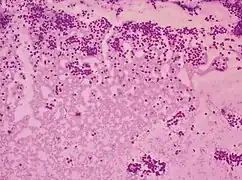

A low-grade squamous intraepithelial lesion (LSIL or LGSIL) indicates possible cervical dysplasia. LSIL usually indicates mild dysplasia (CIN 1), more than likely caused by a human papillomavirus infection. It is usually diagnosed following a Pap smear.

CIN 1 is the most common and most benign form of cervical intraepithelial neoplasia and usually resolves spontaneously within two years. Because of this, LSIL results can be managed with a simple "watch and wait" philosophy. However, because there is a 12–16% chance of progression to more severe dysplasia, the physician may want to follow the results more aggressively by performing a colposcopy with biopsy.[7] If the dysplasia progresses, treatment may be necessary. Treatment involves removal of the affected tissue, which can be accomplished by LEEP, cryosurgery, cone biopsy, or laser ablation.